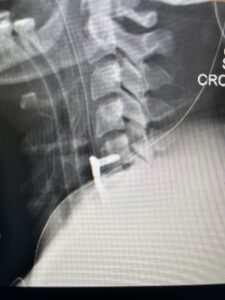

This 47-year-old male who four months prior was lifting weights developed sharp pain in his neck. After that he developed progressive numbness in his arms, neck pain and headache. He said that the right arm was worse than the left. On examination the patient had long tract weakness on the right side which included his triceps, finger extensors, hip flexors, and dorsiflexors. The patient did not have hyperreflexia. MRI (Fig. 2) demonstrated a massive, extruded disc herniation with severe cord compression. The patient because of progressive myelopathy and spinal cord compression was indicated for anterior cervical discectomy and fusion at C4-5 (Fig. 3). Patient had significant improvement of weakness and numbness post operatively.

Fig. 2a Sagittal T2-weighted cervical MRI demonstrating large C4-5 herniated disc with spinal cord compression (red arrow)

Fig. 3 Intraoperative lateral cervical X-Ray demonstrating C4-5 ACDF